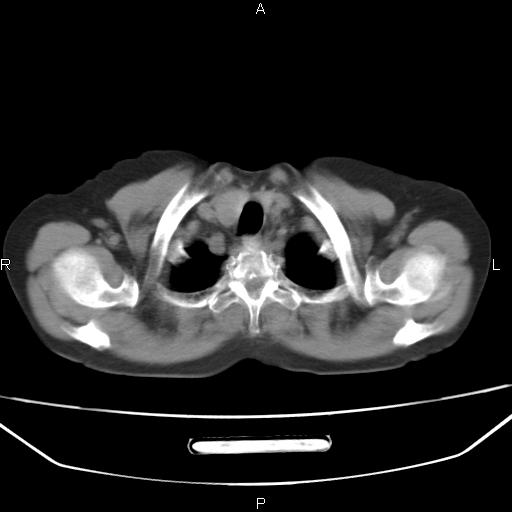

患者,女,66岁。健康体检胸部透视发现右上肺片状阴影。既往无不适,患者自诉三个月前曾有低热病史体温37.5左右一周。用药后缓解。至今无其它不适。请老师们指导指导。

考虑:右肺上叶周围型肺癌(分叶状肿块+砂粒状钙化+胸膜尾征)。

病灶见明显分叶、大小较大(大于3cm?),老年人,多考虑:肺癌,建议穿刺活检。

典型的中心型肺癌,尖段支气管阻塞。

右肺上叶周围型肺癌可能性大。

考虑:右肺上叶周围型肺癌